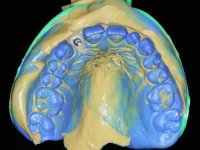

An impression was made on the implant with open tray technique using soft and regular consistency putty. At the laboratory, after confection of the work model, a diagnostic waxing was performed, which sought to find an aesthetic compromise solution. In this sense, a temporary workpiece screwed onto the implant was used to simulate the difficulties we would have with screwing the definitive work. This study abutment consisted of wax to reproduce soft and hard tissues, seeking to anticipate the use of ceramics of gingival and coronary shade. Also, part of the interproximal papillae corresponding to the distal portion of the 2.1 tooth and the mesial tooth of the tooth 2.3 were also waxed, anticipating the use of composite resin “chips” with gingival tonality. Finally, a veneer was waxed to correct the microdontia of the tooth 1.2. In this waxing, the vestibular emergence of the orifice for access to the screw of the implant abutment was evident. Once this therapeutic option was accepted, the implant abutment in polymerized composite resin was prepared at the lab, as well as the papillary "chips", also in composite resin of gingival tonality. Tested in the mouth, the abutment was screwed and the "chips" bonded. The access hole of the screw was filled with composite resin. In subsequent consultation, a gingivectomy was performed on the cervical contour of teeth 1.3, 1.2 and 1.1 with the aim of correcting the asymmetry between the first and second quadrant. After the soft tissues were cicatrized, a dental bleaching was performed according to the patient’s aesthetic requirements. Final impression on the implant was made using the silicone open tray technique, taking care to individualize the transfer piece by copying the emergence profile of the patient’s provisional abutment. At the laboratory, the impression yielded a definitive working model, on which the abutment was waxed on a plastic insert. This process was carried out with the orientation of a wall of silicone based on diagnostic waxing. The wax made on the plastic part was placed in a special holder that allowed its scanning in a laboratory scanner. This scan by CAD process informed the design of an abutment in Zr. later materialized by a CAM process. The Zr. abutment was tested in the mouth, validating its clinical and imaging establishment. During this consultation, the choice of color was made by the ceramist, of both the coronary ceramics and the ceramic of gingival tonality to be used. Individualized color scales were used. At the laboratory, the coronary and gingival ceramics were placed on the implant abutment and later, on a working model with refractory gypsum, a veneer of feldspathic ceramic was made. This veneer was built on a surface specially designed for this purpose in the abutment. This surface tried to reproduce a dental preparation performed for the same effect. In the mouth the abutment was screwed with a torque of 35N, the access hole to the screw was filled with Teflon and later filled with composite resin. The veneer was bonded onto the implant abutment using the conventional bonding technique, with relative insulation. For economic reasons, the patient did not proceed to perform the veneer on tooth 1.2. Although a limited aesthetic compromise was expected from the outset, a result was achieved which satisfied the patient.